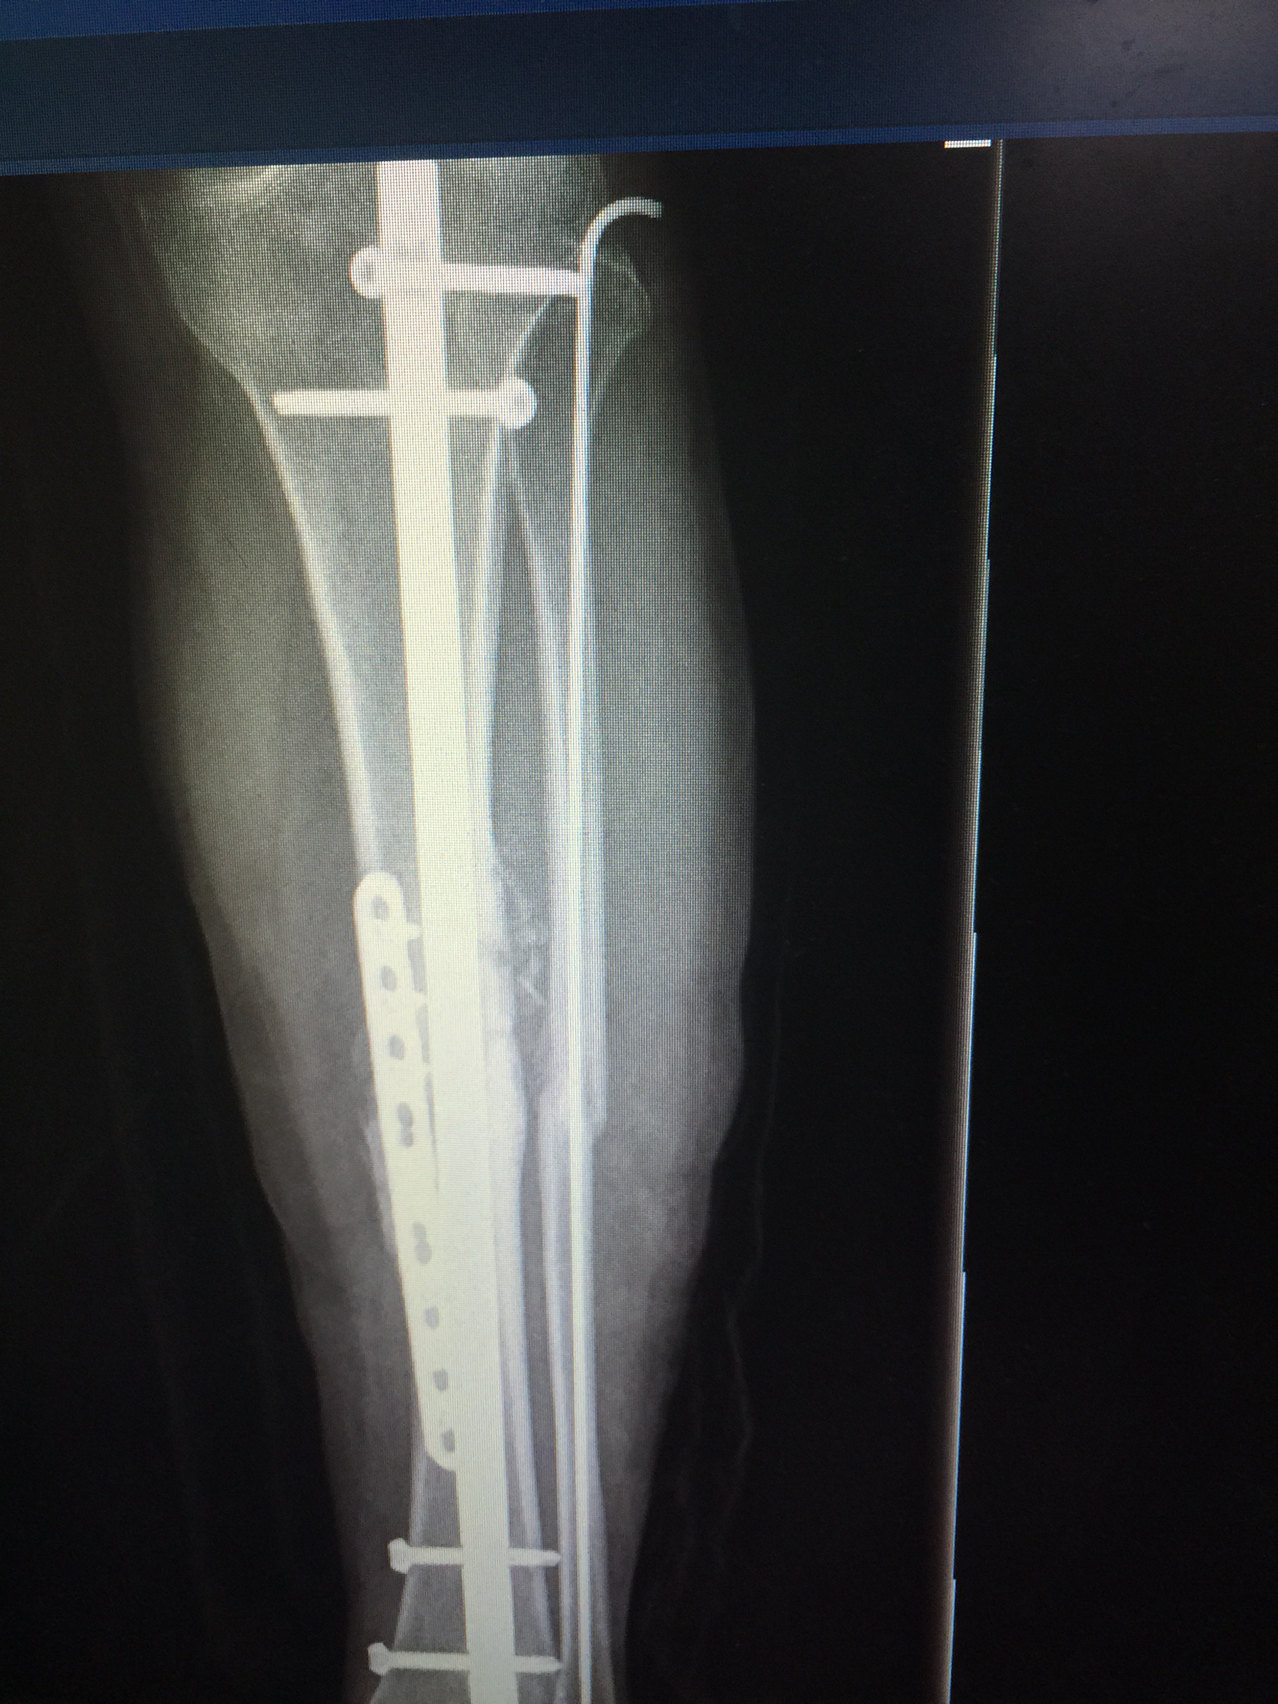

自分の場合、脛骨、腓骨、関節外果(2箇所)の計4箇所を骨折してしまいました。 ostra3さんと同様、骨折観血的手術を行い、現状右足はプレート2枚が入り、ボルトだらけになっています(笑)。 骨折記、拝見させていただきました。 色々と大変なんですね。下は脛骨というスネの骨にくっついており、 主に剥離骨折は、 脛骨側で起こりますので、 今回の前十字靱帯の付着部は 脛骨となります。 その脛骨の関節面にくっついています。 これは1つ特徴ですね。 前十字靱帯付着部剥離骨折の症状は?夫が転んで足を骨折し、入院・手術しました。 その経過記録です。 (水) お昼過ぎに「足怪我して今病院にいる」と電話が入る。 この日はたまたま母が整形外科の通院日になっており、夫は病院で私の両親と会い、事情を話して父がウチまで迎えに来てくれると言うので、仕度をして

手術の適応となることがあります。 脛骨内側顆疲労骨折 脛骨内側顆(けいこつ ないそくか)とは膝よりやや下の内側の部分です。この部位の疲労骨折はランニング、ウォーキングでみられます。骨粗鬆症などが背景にある場合が多いとされています。完全脛骨腓骨を骨折し、抜釘手術で1年2ヶ月ぶりにプレートが外れました。 抜釘手術後の経過 所要時間;1時間程度。前回の手術、プレート固定術の1/3。 麻酔方法;全身麻酔と神経ブロック。(前回は全身麻酔と硬膜外麻酔)負担の少ない手術であったはず。左脛骨疲労骨折 全治 手術後約4ヶ月の見込み コメント 今回の発表のとおり、昨年5月に行った手術と同じ場所を手術しました。前回よりも頑丈にする手術です。

自分の場合、脛骨、腓骨、関節外果(2箇所)の計4箇所を骨折してしまいました。 ostra3さんと同様、骨折観血的手術を行い、現状右足はプレート2枚が入り、ボルトだらけになっています(笑)。 骨折記、拝見させていただきました。 色々と大変なんですね。でも、手術した足の方がまだ感覚は鈍くて、触られても、 なんとなく、触られよるかも?? な、感じ。 これは、背中から注入中の痛み止めが原因なんだとか。 当たり前やけど、 脛骨骨折手術した足は むちゃくちゃ腫れとります!「ORIF」とは、"Open Reduction and Internal Fixation"の略です。Open=開けて、Reduction=補正して、Internal=内部を、Fixation=固定する、文字通り、皮膚を切開して開き、骨を直接固定する手術方法で、「観血的骨接合術」と言います。今回は、「ORIF」とは?そしてその手術方法などについて解説します。

脛骨腓骨骨折 髄内釘 抜釘手術の費用や治療後の経過についてレポート にちプチ Nichi Petit

胫骨骨折翻修 博美 采用hyprotect Prcl S银离子抗菌骨板系统进行内固定手术 蒋祖龙医生 Bluesao 佰陆

两例胫腓骨骨折治疗的选择 刻骨甘露 微信公众号文章阅读 Wemp